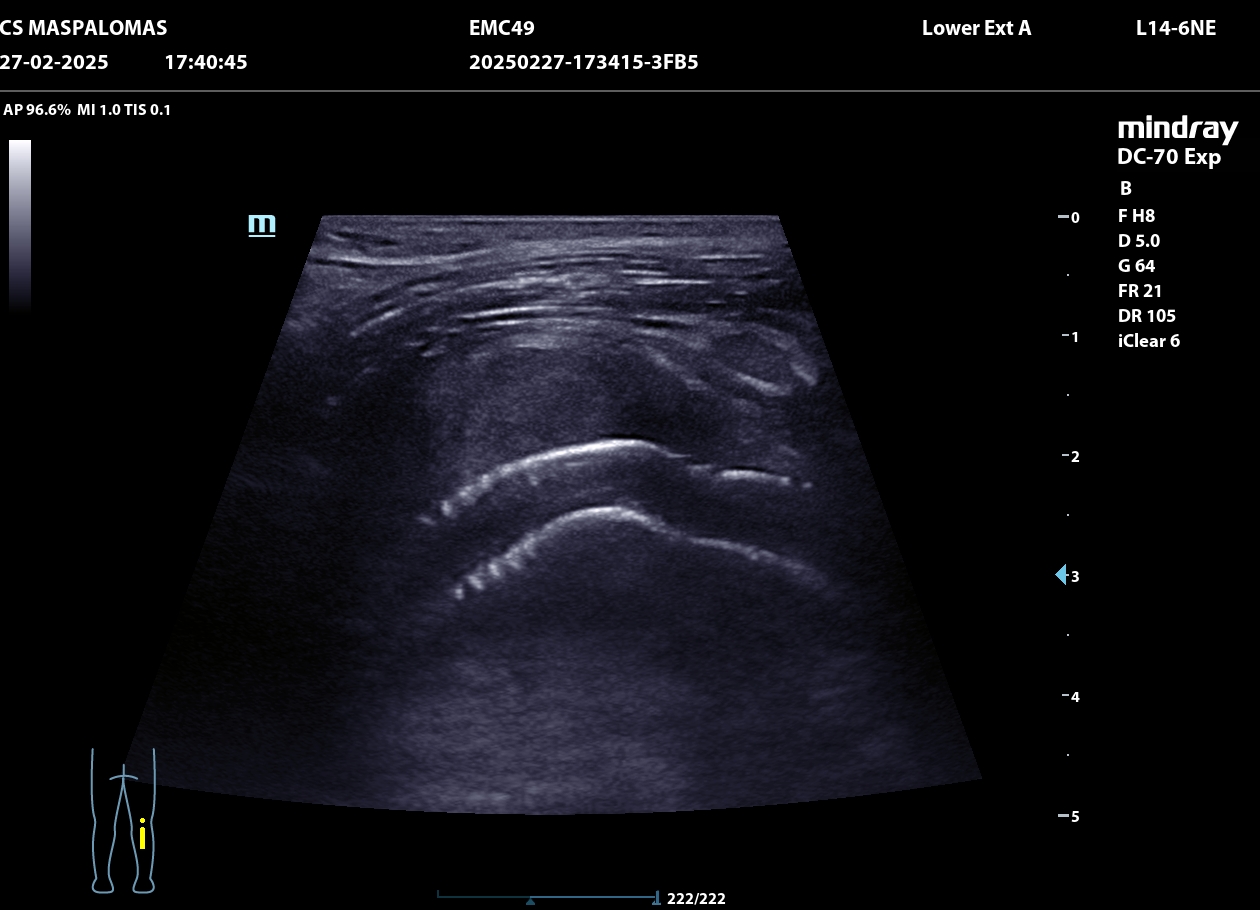

Se realiza ecografía clínica en consulta que revela un aneurisma de la arteria poplítea derecha de 4,66 cm con trombo intraluminal de gran tamaño.

El paciente es derivado a urgencias hospitalarias, se realiza un ECO-Doppler que muestra dilatación de la arteria poplítea derecha de 3 cm con trombo mural, y durante el ingreso en Cirugía Vascular un TAC, confirmando la presencia de un pseudoaneurisma de arteria poplítea derecha de 4,70 x 3,80 cm con trombo mural y salida distal por tres vasos.